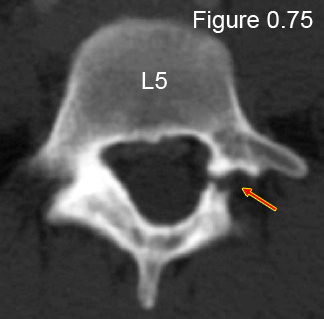

Blown out is my description of being herniated past the point of being repairable.Blown out, herniated ---- same thing. Romo had a microdiscectomy, for extraction of impinging fibrous disc material.

The disc simply provides cushion between the vertebrae. At least half of all disc herniations do not require surgery. Surgery is required when the disc has degenerated enough to allow displacement of one vertebra vs another, thereby causing nerve impingement, or if extruded disc material causes nerve impingement. The impingement may lead to deterioration of the nerve and the subsequent musculature, and therefore needs to be addressed.